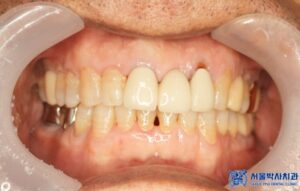

오늘은 오래전에 하악 어금니를 발치하고

그 상태로 지내시다가,

전체적으로 치료를 받으러 오신 환자분의

임플란트 치료 및 신경 치료 사례를

소개해 드리도록 하겠습니다.

위 환자분께서는 오랫동안 없던 어금니뿐만 아니라

나머지 불편한 치아들도 함께 치료를 원하셨는데요.

이러한 장점 덕분에 환자분도

완성된 크라운의 색상과 모양, 착용감 등

모두 만족스럽다고 하셨습니다.

환자분은 전체적인 치료를 마친 후,

전체적으로 치아가 건강해진

느낌이 든다고 말씀하셨습니다.